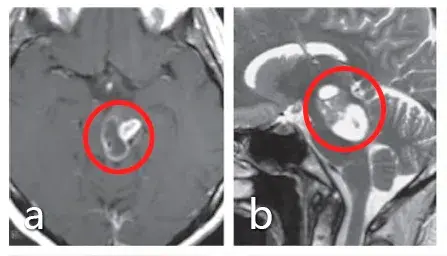

医生,孩子刚才还好好的,突然就哭喊着说自己头痛,好像下一秒就要痛晕过去了一样,你快救救他!急诊室内的一幕令众人纷纷侧目,一位神色慌张的母亲正搀扶着她年幼的儿子,而这竟差点...

一年多前,10岁的安格因呕吐被查出第四脑室肿瘤,在接受分流术后的第5天,安格被再次推入手术室,成功全切了肿瘤,病理报告显示为低级别胶质瘤。然而安格一家看似有惊无险的治疗之路,...